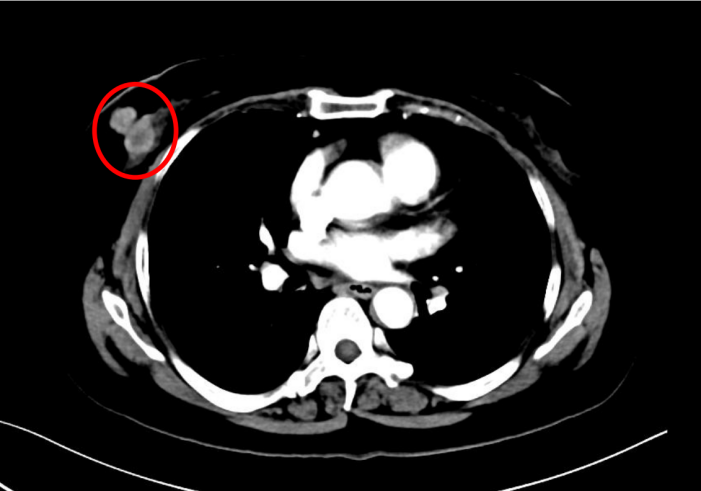

患者为女性,60岁,已绝经,既往史无特殊。2021年5月10日于院内行乳腺及淋巴结彩超检查,提示右乳腺实性结节(BI-RADS 4C级)及右腋下肿大淋巴结。进一步影像学评估显示,右乳原发灶大小约2.7×2.3 cm,右腋窝淋巴结约1.8×1.3 cm;同时可见双肺结节,最大约0.9×0.7 cm,并见右肺门淋巴结约1.1×1.0 cm。整体影像学结果提示患者初诊时已存在乳腺原发灶伴区域淋巴结及肺部转移。

图1:右乳腺肿物

治疗2个月后影像学复查结果示:右乳腺原发灶由2.7 × 2.3 cm缩小至2.4 × 2.1 cm;右腋窝淋巴结由1.8 × 1.3 cm缩小至1.3 × 0.9 cm;右肺中叶结节由0.9 × 0.7 cm缩小至0.7 × 0.6 cm;右肺门淋巴结由1.1 × 1.0 cm缩小至1.0 × 0.9 cm。本次复查显示乳腺原发灶缩小11%腋窝淋巴结、肺病灶、右肺门淋巴结均缩小。总体疗效评估为疾病稳定(SD)。这提示患者在治疗早期即出现客观影像学改善,但尚未达到部分缓解(PR)阈值。

截至治疗4年6个月时,患者仍维持持续获益。右乳腺原发灶缩小至0.6 × 0.5 cm;右腋窝淋巴结缩小至0.4 × 0.3 cm;右肺中叶原结节影未再显示;右肺门淋巴结缩小至0.7 × 0.4 cm。本次复查显示乳腺原发灶缩小78%;腋窝淋巴结、肺病灶、右肺门淋巴结影像学CR。总体疗效评估为持续PR。